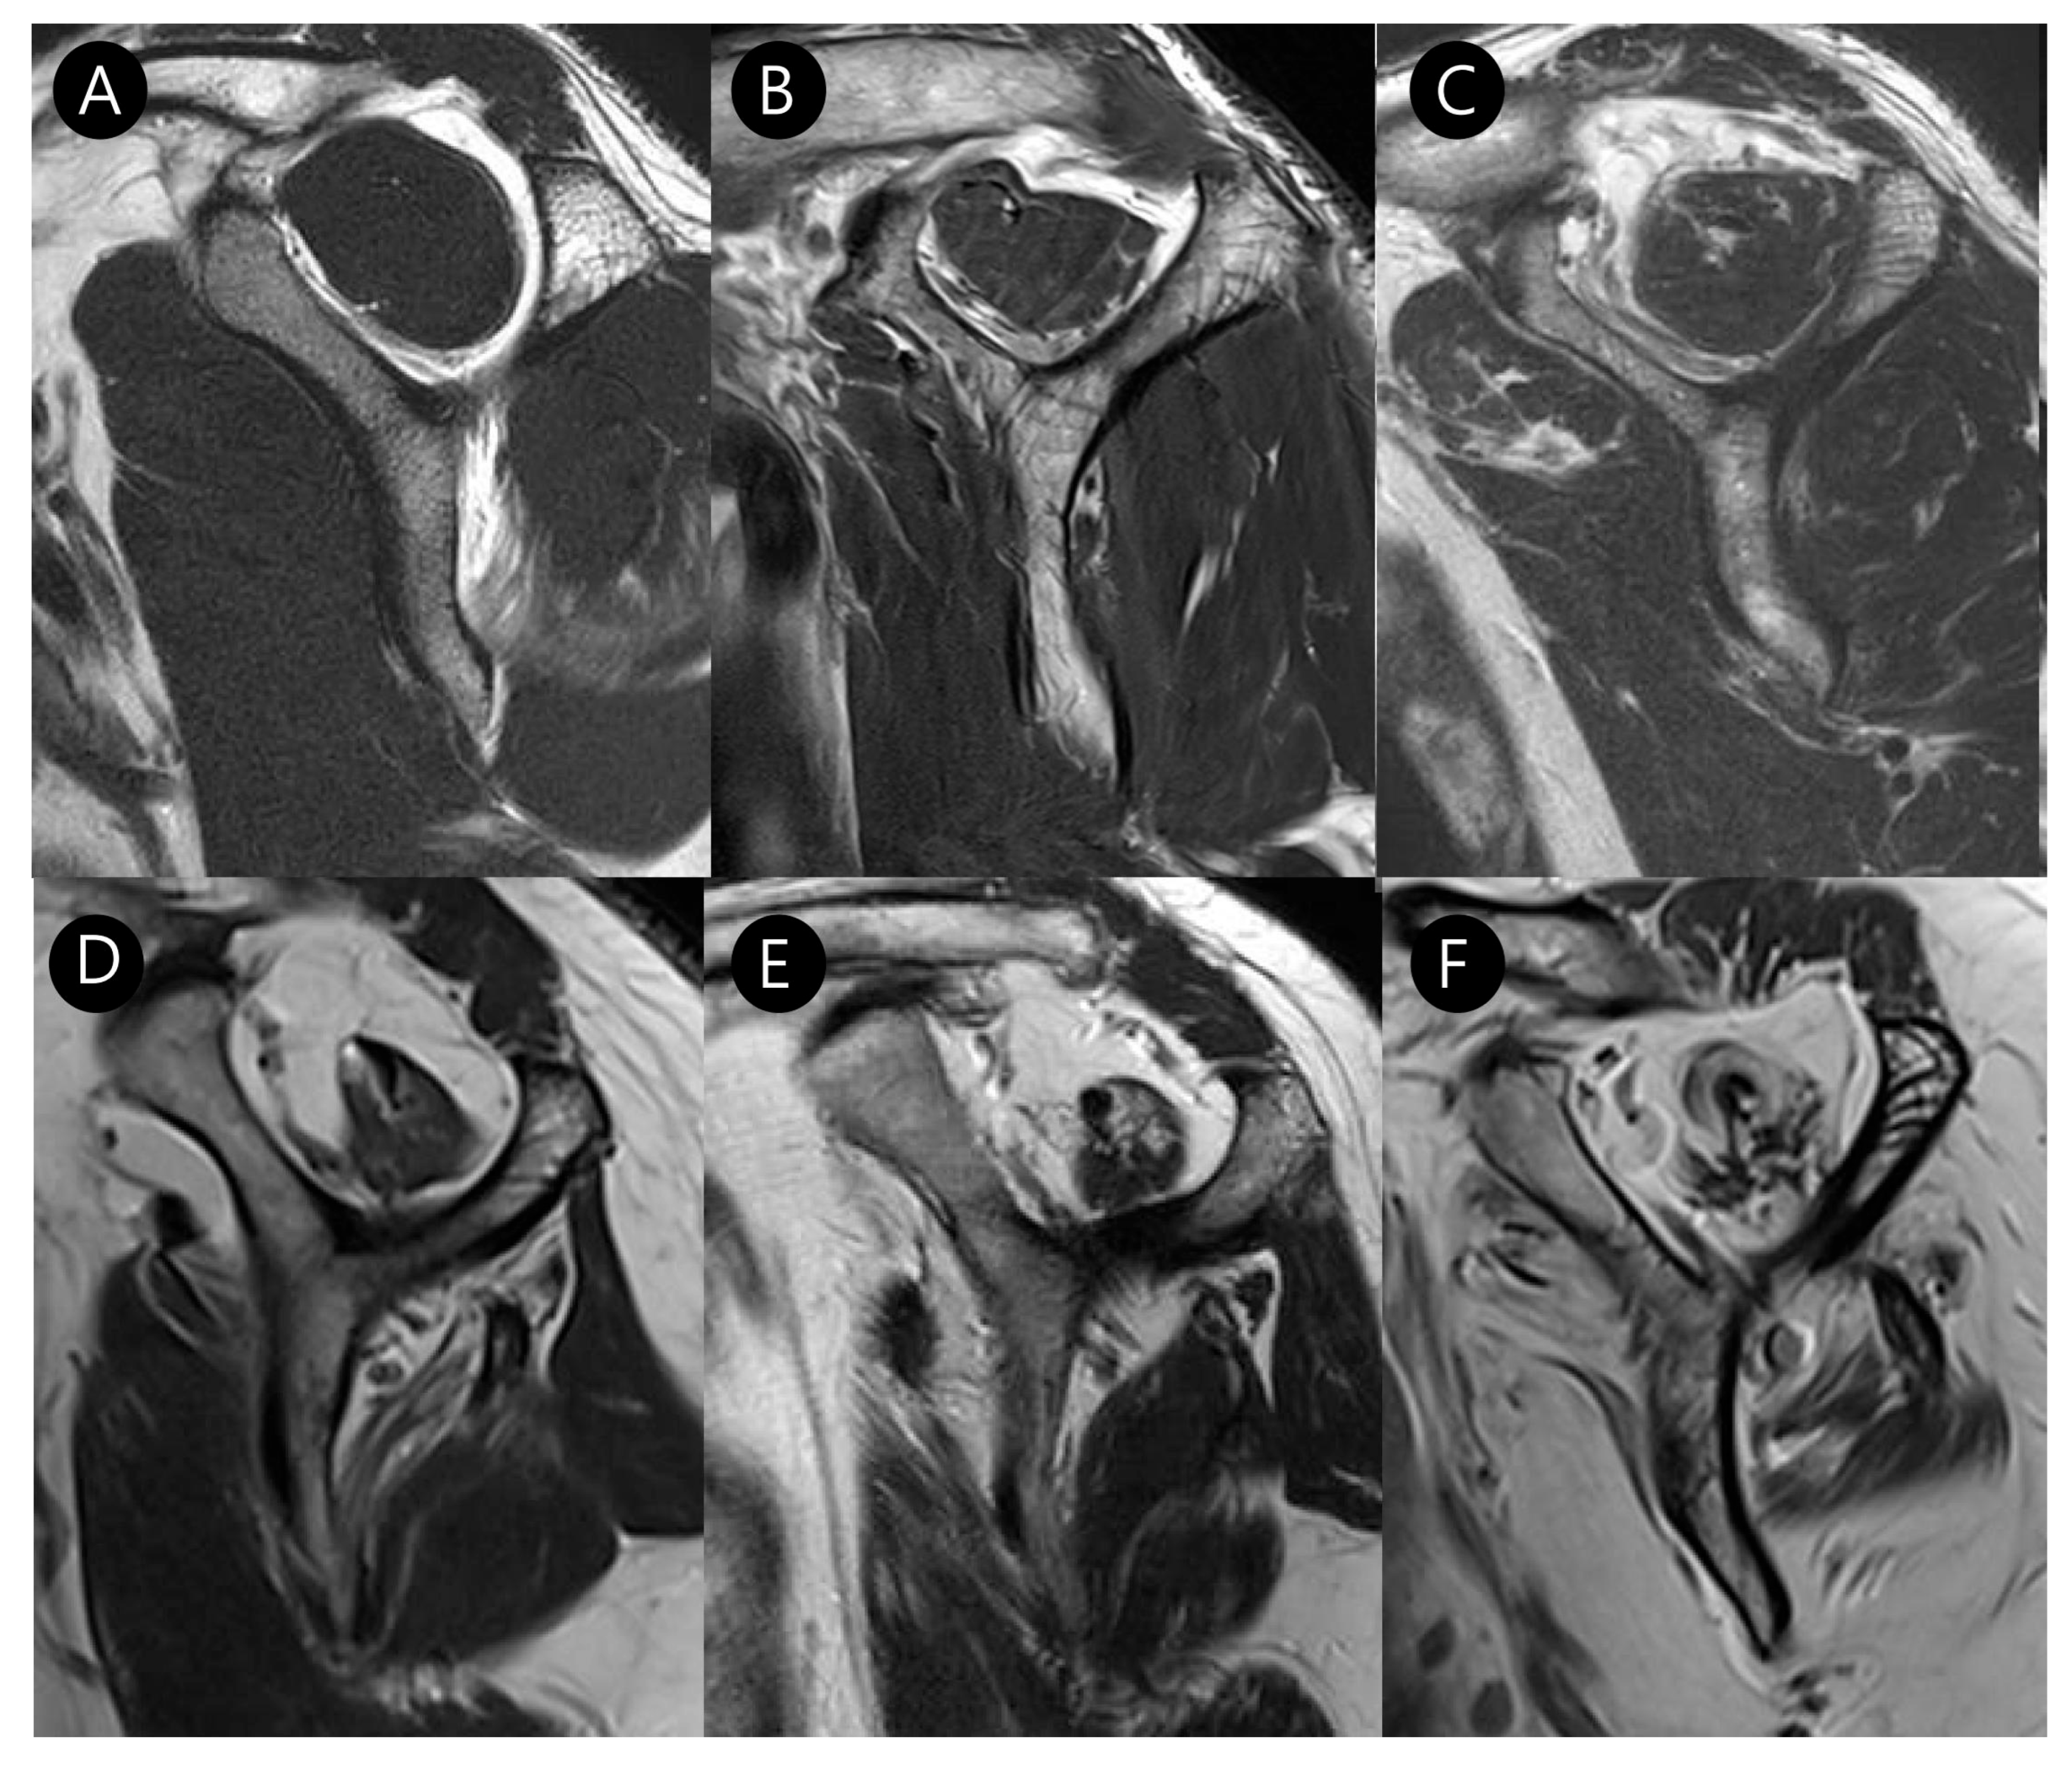

3.2. MRI Findings

| Long head biceps tendon pathologies | ||||

| Full thickness tear (%) | 4 (3.6) | 5 (15.6) | 0.040 | κ = 1.000 (p < 0.001) |

| Partial thickness tear (%) | 47 (43.9) | 25 (92.6) | <0.001 | κ = 0.981 (p < 0.001) |

| Tendinosis (%) | 76 (71.0) | 27 (100.0) | 0.003 | κ = 0.899 (p < 0.001) |

| Subluxation or dislocation (%) | 13 (12.1%) | 22 (81.5%) | <0.001 | κ = 0.853 (p < 0.001) |